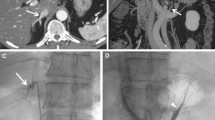

A 56-year-old man with primary aldosteronism. A Contrast-enhanced CT prior to AVS clearly depicts the anatomy of the RAV (arrow). B The catheter venogram demonstrates the right adrenal vein (RAV). C Intraprocedural CT was obtained during AVS to confirm proper catheterization of the RAV referring the direction of the catheter and the CECT images before AVS

Baseline venous sampling through the RAV was performed after confirmation of successful and accurate catheterization on unenhanced CT images. After the baseline venous sampling, 0.25 mg cosyntropin was injected via a peripheral venous line, and post-stimulation venous sampling through the RAV was obtained. During venous sampling, proper catheter positioning was verified and occurrence of catheter malpositioning was carefully checked on fluoroscopy. Success of AVS was defined as successful catheterization and venous sampling from the RAV followed by biochemical success. Biochemical success was defined as satisfying the following established criteria: a selectivity index (ratio between the adrenal veins and the distal IVC plasma cortisol concentrations) ≥ 5 after cosyntropin stimulation [11, 12].

A 42-year-old woman with primary aldosteronism (classified into the “presumed RAV group”). A Contrast-enhanced CT prior to AVS depicts the anatomy of the right adrenal vein (RAV) (arrow). B The catheter venogram demonstrates that the catheter is presumably cannulated in the RAV. C. Intraprocedural CT reveals that the catheter is not accurately positioned into the RAV but into accessory hepatic vein. D The catheter venogram after catheter repositioning demonstrates that the catheter is presumably cannulated in the RAV. E Intraprocedural CT after catheter repositioning reveals accurate catheterization of the RAV with reference to the CT images before AVS

A 40-year-old woman with primary aldosteronism (classified into the “obscured RAV group”). A Contrast-enhanced CT prior to AVS clearly depicts the anatomy of the RAV (arrow). B The first catheter venogram shows that the retroperitoneal vein is visualized and catheterization of the RAV was uncertain. C Intraprocedural CT reveals that the catheter is not accurately positioned into the RAV but into the retroperitoneal vein. D The catheter venogram after catheter repositioning demonstrates that the catheter is presumably cannulated in the RAV, which communicates with retroperitoneal veins. Operator considered that the retroperitoneal veins obscure obvious visualization of the RAV. E Intraprocedural CT after catheter repositioning verifies the accurate and definite catheterization of the RAV

A 63-year-old woman with primary aldosteronism (classified into the “obscured RAV group”). A Contrast-enhanced CT prior to AVS cannot depict the anatomy of the RAV. B The catheter venogram demonstrates development of the retroperitoneal veins and the visualization of the RAV is unclear. C Intraprocedural CT reveals accurate catheterization of the RAV, in which the microcatheter reaches the right adrenal gland